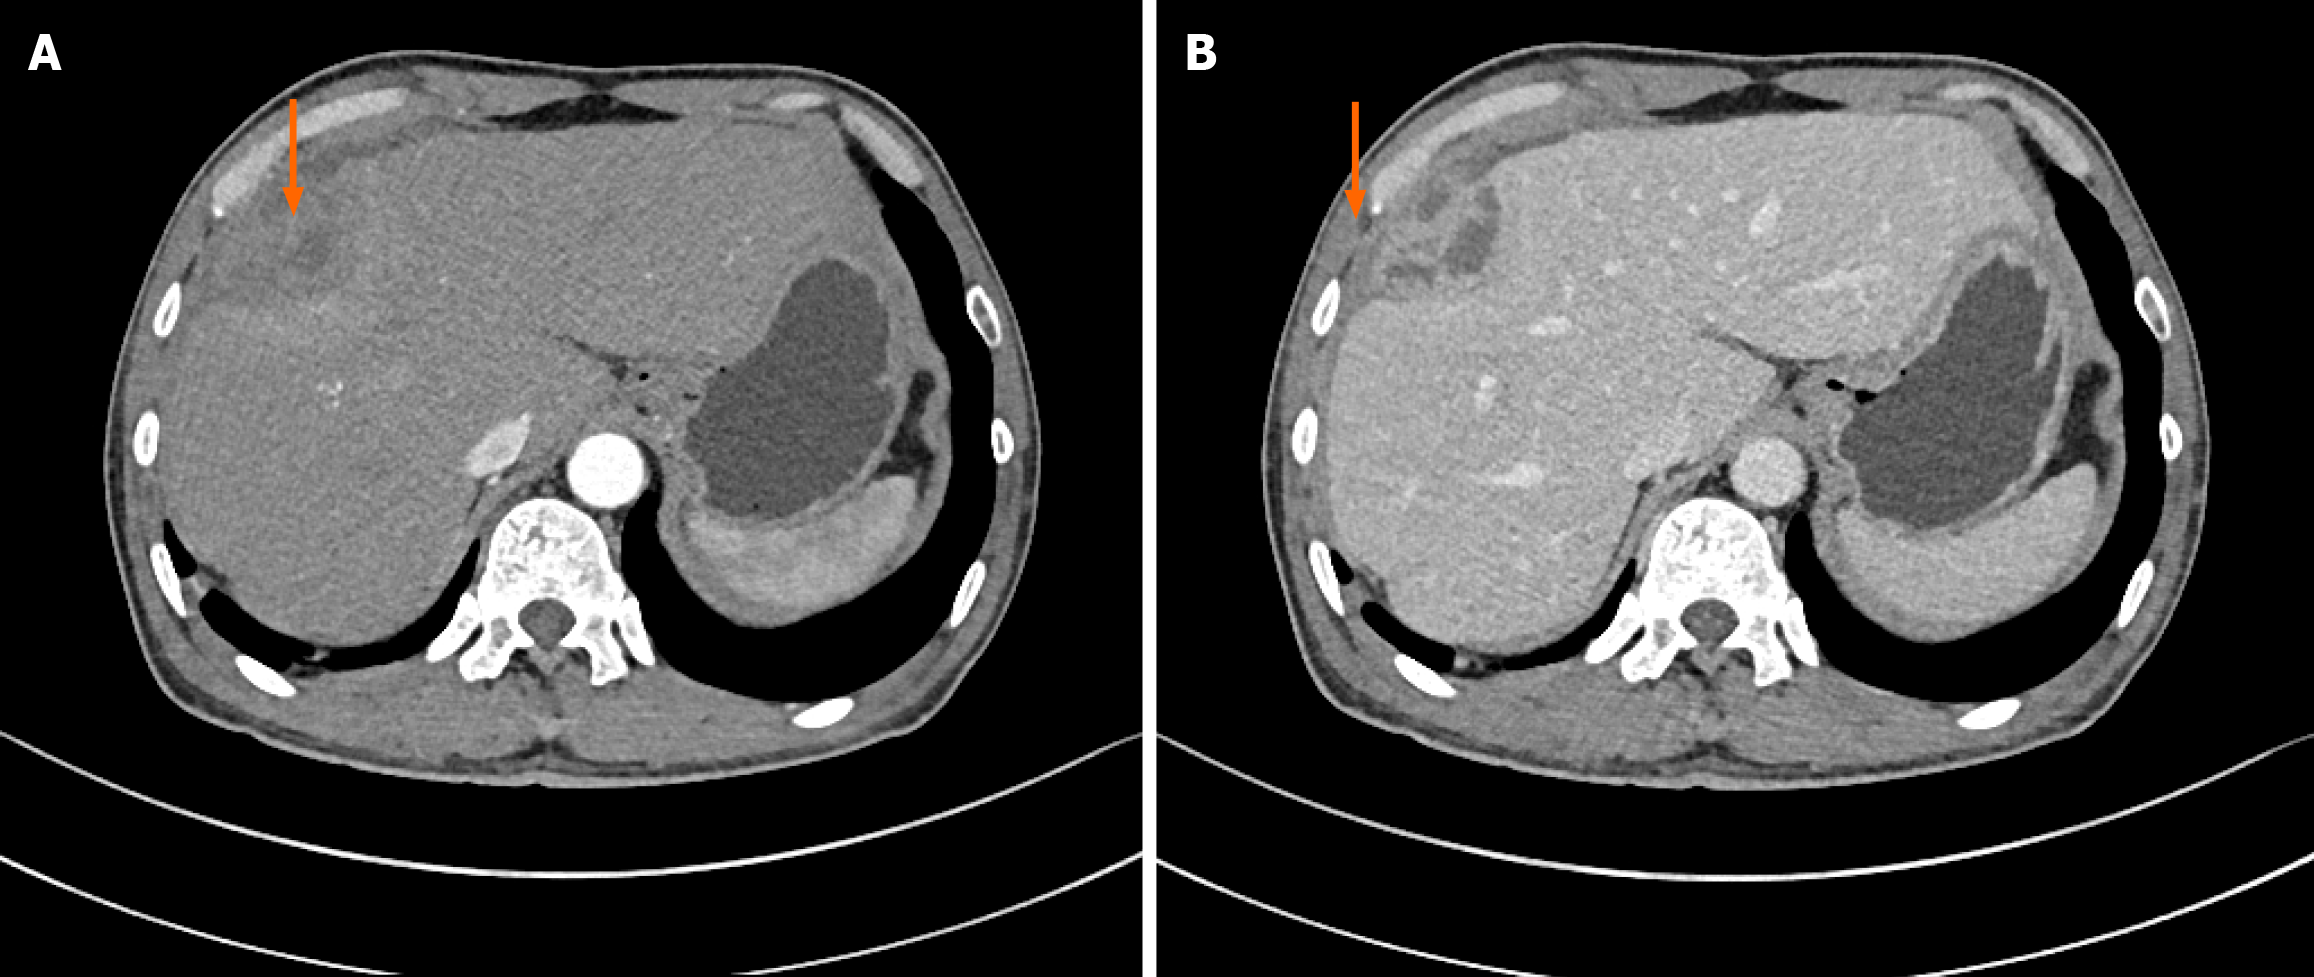

Ostoperative laboratory tests showed that the patient’s liver function and coagulation function were only mildly abnormal: Albumin 30.6 g/L; aspartate aminotransferase 159 U/L; plasma prothrombin time 13.3 seconds; prothrombin time activity 65.1%. The patient was discharged six days after surgery, and no recurrence or metastasis was observed during follow-up 1 month, 3 months, and 6 months after surgery (Figures 3 and 4).